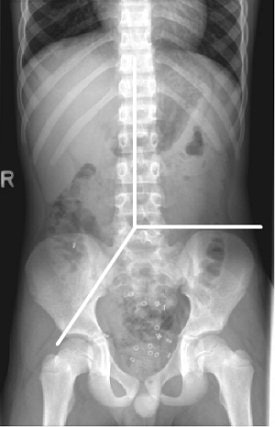

![]() |

| The Bouchoucha method was used to determine CTT. Here, the day 7 radiograph was used to count the number of markers visible in the colon. The number of markers multiplied by 2.4 produced the total CTT hours. A CTT of more than 62 hours was considered delayed. The Leech method scoring method was applied to the right colon, the left colon, and the rectosigmoid segment. Image courtesy of Dr. Fleur de Lorijn, Ph.D. |